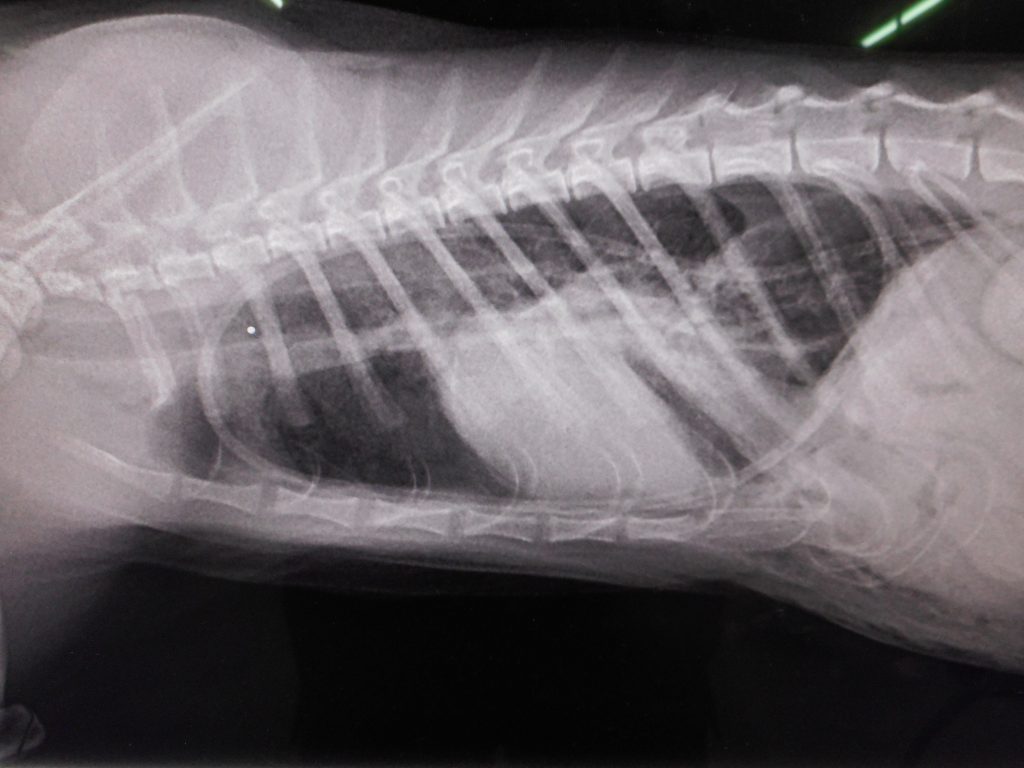

横隔膜ヘルニアの仔猫

息苦しくなっての手術

手術後の写真は

心臓が診えて、黒い肺の部分も出てきました

胸腔ドレーンもバッチリ

・・・・・・・、急死してしまいました

it was cat’s diaphragmatic hernia.

it died suddenly……